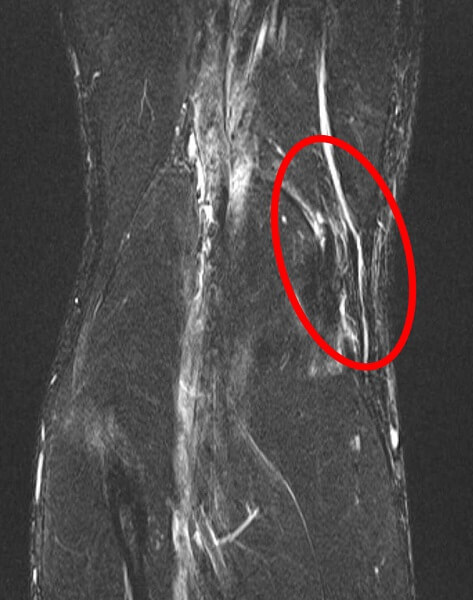

MRI画像

鵞足の腱周囲の炎症による輝度上昇(白く見える)が確認できる。